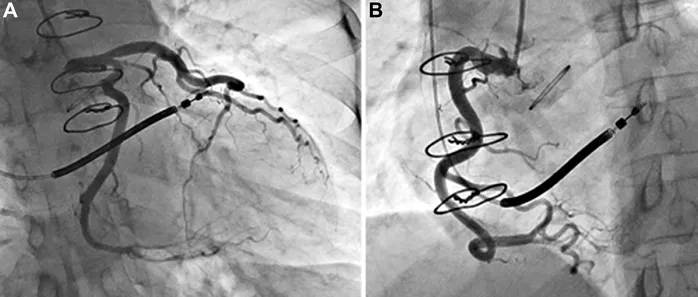

针对心尖部室壁瘤的典型症状,鉴别诊断需重点排除以下常见病因:1)肥厚型梗阻性心肌病:经胸超声心动图显示巨大解剖性心尖前壁室壁瘤,约占左心室容积60%,伴收缩期反常运动,根据该表现排除肥厚型梗阻性心肌病诊断(图1、2);2)冠状动脉疾病:冠脉造影提示未见明显狭窄、心肌桥或血流异常,据此排除冠状动脉相关疾病(图2)。

图2 术前冠状动脉造影